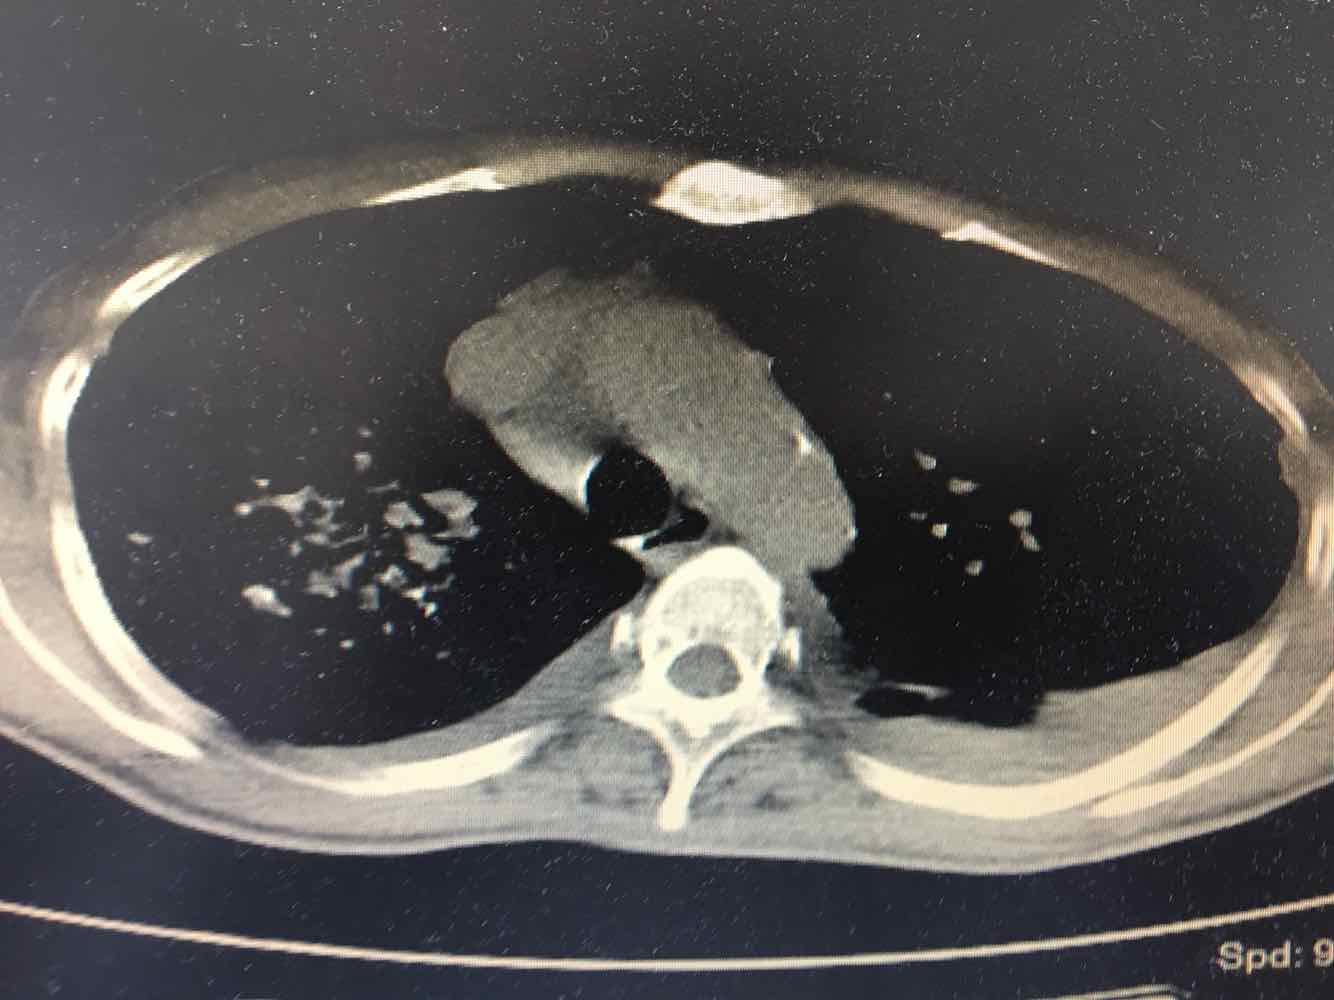

女,51岁,支气管扩张病史多年。慢性咳嗽咳痰喘息30年,加重1个月,无发热,气短为主,痰液不多,上腹不适,少尿。双肺干湿罗音。

图片

慢性肺源性心脏病

1/7

2/7

3/7

4/7

5/7

6/7

7/7